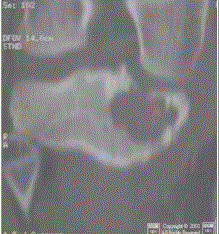

问题 患者男,15岁。右膝X线平片和CT检查见下图。 此病变最可能的诊断是

选项 A.骨巨细胞瘤 B.内生软骨瘤 C.骨结核 D.成软骨细胞瘤 E.软骨黏液样纤维瘤

答案 D